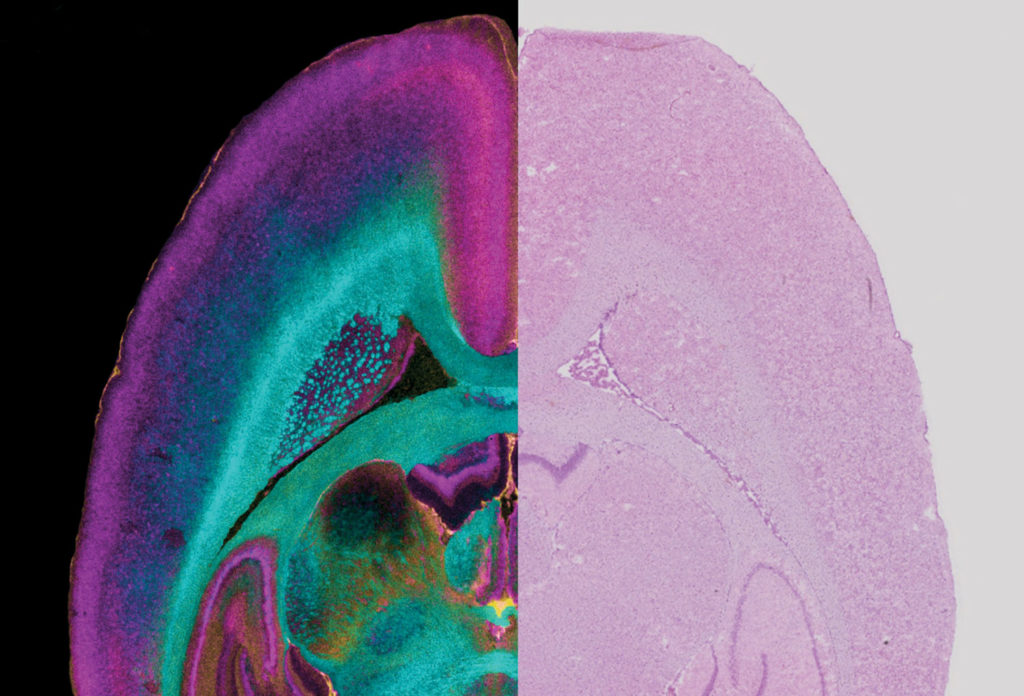

From news.vanderbilt.edu

Up Close and Personal Vanderbilt explores the frontiers of imaging technology Vanderbilt Vanderbilt Medical Imaging Library find searching tutorials for various databases, information on endnote, mendeley, and zotero, or contact a librarian. center for human imaging. The human imaging core (hic) provides resources for structural and functional imaging and spectroscopy. the eskind biomedical library provides information resources and services for the vanderbilt university school of medicine, school of nursing, and medical center. . Vanderbilt Medical Imaging Library.